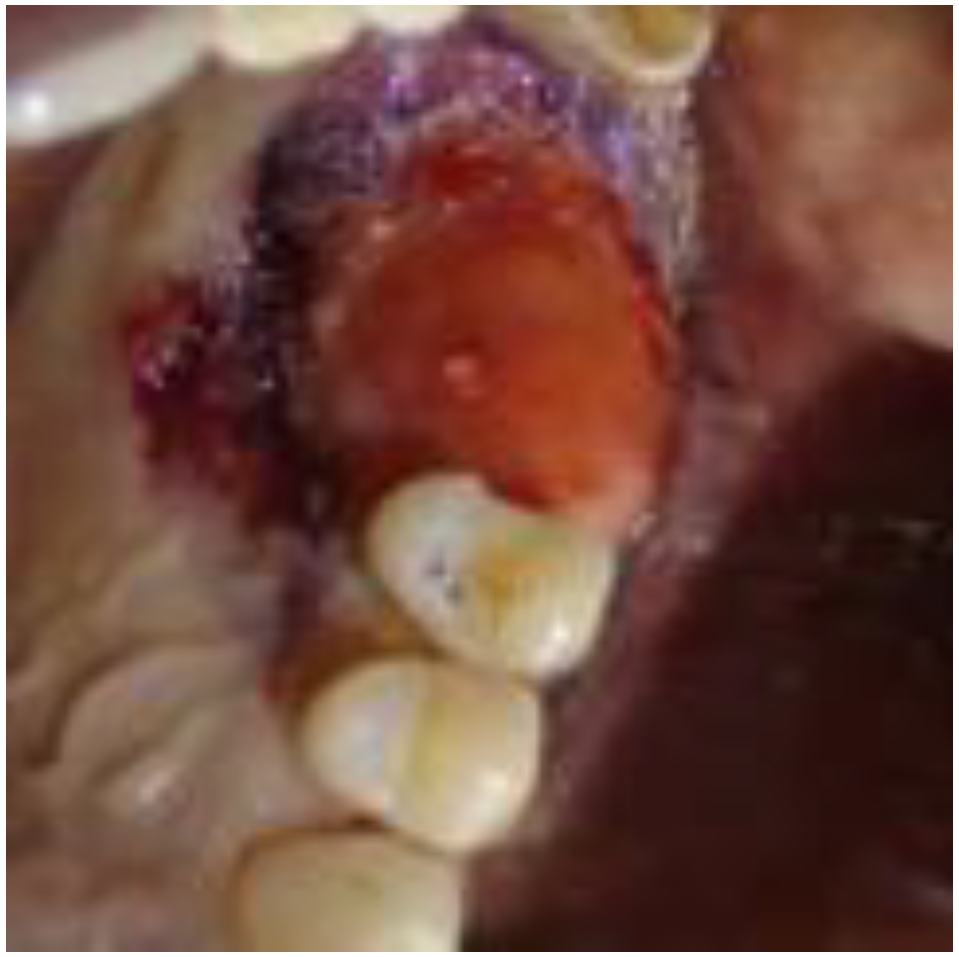

2.1. Clinical and Surgical Procedures